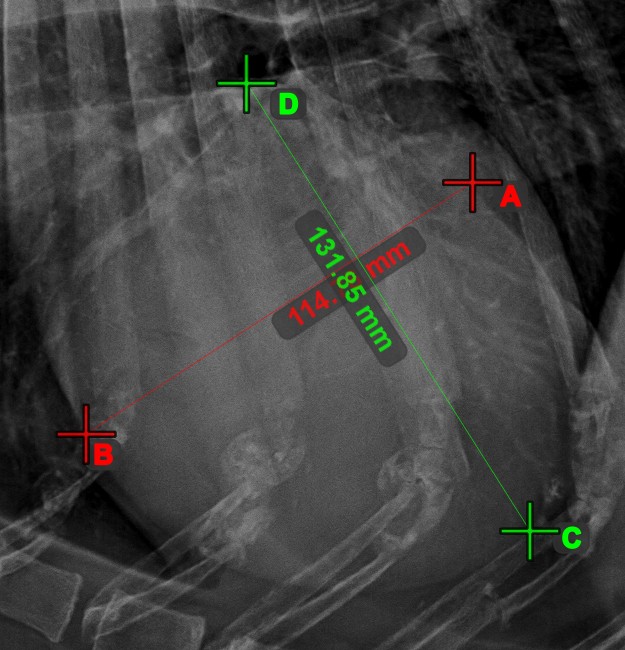

Circle from 3 Points¶

The Circle from 3 Points

tool is a simple and effective way to create a circle from just three points.

Start by selecting the tool from the left toolbar and assign it to one of the available mouse buttons. Place the three points of the circle, or select the points from ones available on the scene. The circle will be automatically created based on the position of the three points. The origo of the circle will always be marked with O. The radius of the circle is automatically calculated.

Modify the position of the three points to change the radius of the circle by using the Select/Move Item

tool.